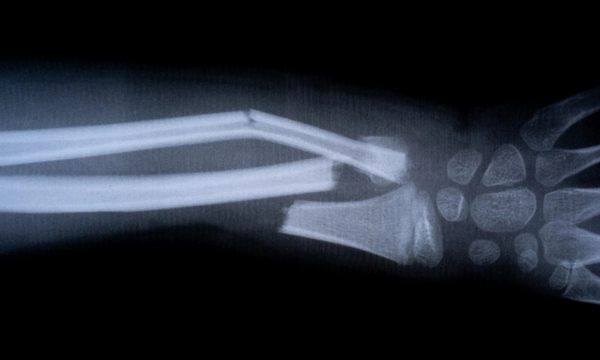

Trong một trường hợp thử nghiệm đáng chú ý được Cho Sun Daily đưa tin, một bệnh nhân bị gãy cổ tay đã được tiêm một mũi qua một vết rạch dài 3 cm. Vết thương đã được cố định và lành lại chỉ trong 3 phút.

Thông thường, phẫu thuật sửa chữa cổ tay đòi hỏi phải nẹp vít, dẫn đến một cuộc phẫu thuật thứ hai vào năm sau để tháo chúng ra. Tuy nhiên, sau 3 tháng kiểm tra theo dõi, vết gãy xương của bệnh nhân trên đã lành hoàn toàn mà không gặp biến chứng nào.